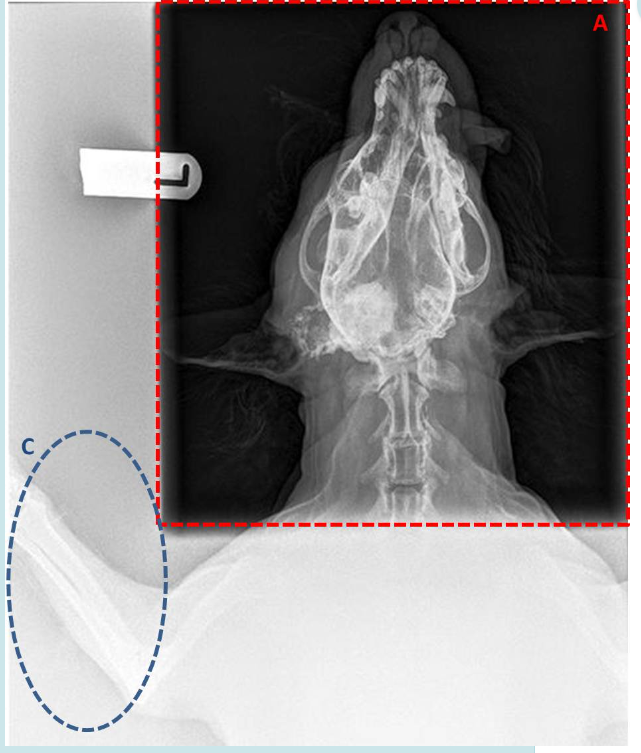

A. Is the image in the area marked A created by the primary or secondary x-ray beam?

B. Will protective clothing (gloves, gowns) stop X-rays within area A?

C. What effect is mainly responsible for producing the image seen in Area C?

D. What piece of equipment can be used to reduce the production of images such as that seen in area A, while maintaining a diagnostic image in area A?

A. Primary

B. No

C. Compton Effect

D. Grid